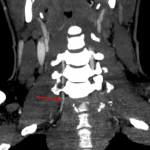

- Mildly displaced avulsion fracture of the left C5 transverse process posterior tubercle

- Multiple small avulsion fractures associated with the C6 inferior and C7 superior articulating facets

- Bilateral posterior first and second rib fractures

Multiple small associated avulsion fractures including left C5 transverse process, C6 spinous process, and bilateral tiny C6 and C7 facet fractures.

Given the above described malalignment, neck CTA is recommended to assess for vascular injury.